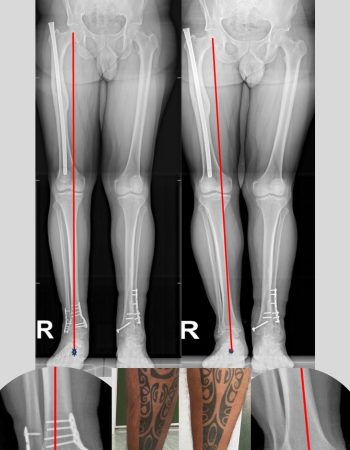

Se objetiva mediante las pruebas de imagen una artrosis asimétrica de tobillo en varo con una inclinación talar (tilt talar) de 9º correspondiente a un grado IIIB de Takakura.

Dada su edad y la existencia de una artrosdesis en el tobillo contralateral decidimos una cirugía de preservación articular mediante plafondplastia de apertura medial. Se asoció osteotomía valguizante de peroné, osteotomía calcánea percutánea valguizante y reconstrucción de ligamento lateral del tobillo mediante aloinjerto como recomiendan las últimas publicaciones en la literatura en casos similares.

Como podéis ver en las imágenes se consiguió mejorar el eje del talón trasladando el eje de carga de al extremidad hacia la zona del tobillo más sana. A pesar de no corregir del todo el tilt talar el paciente se encuentra asintomático.